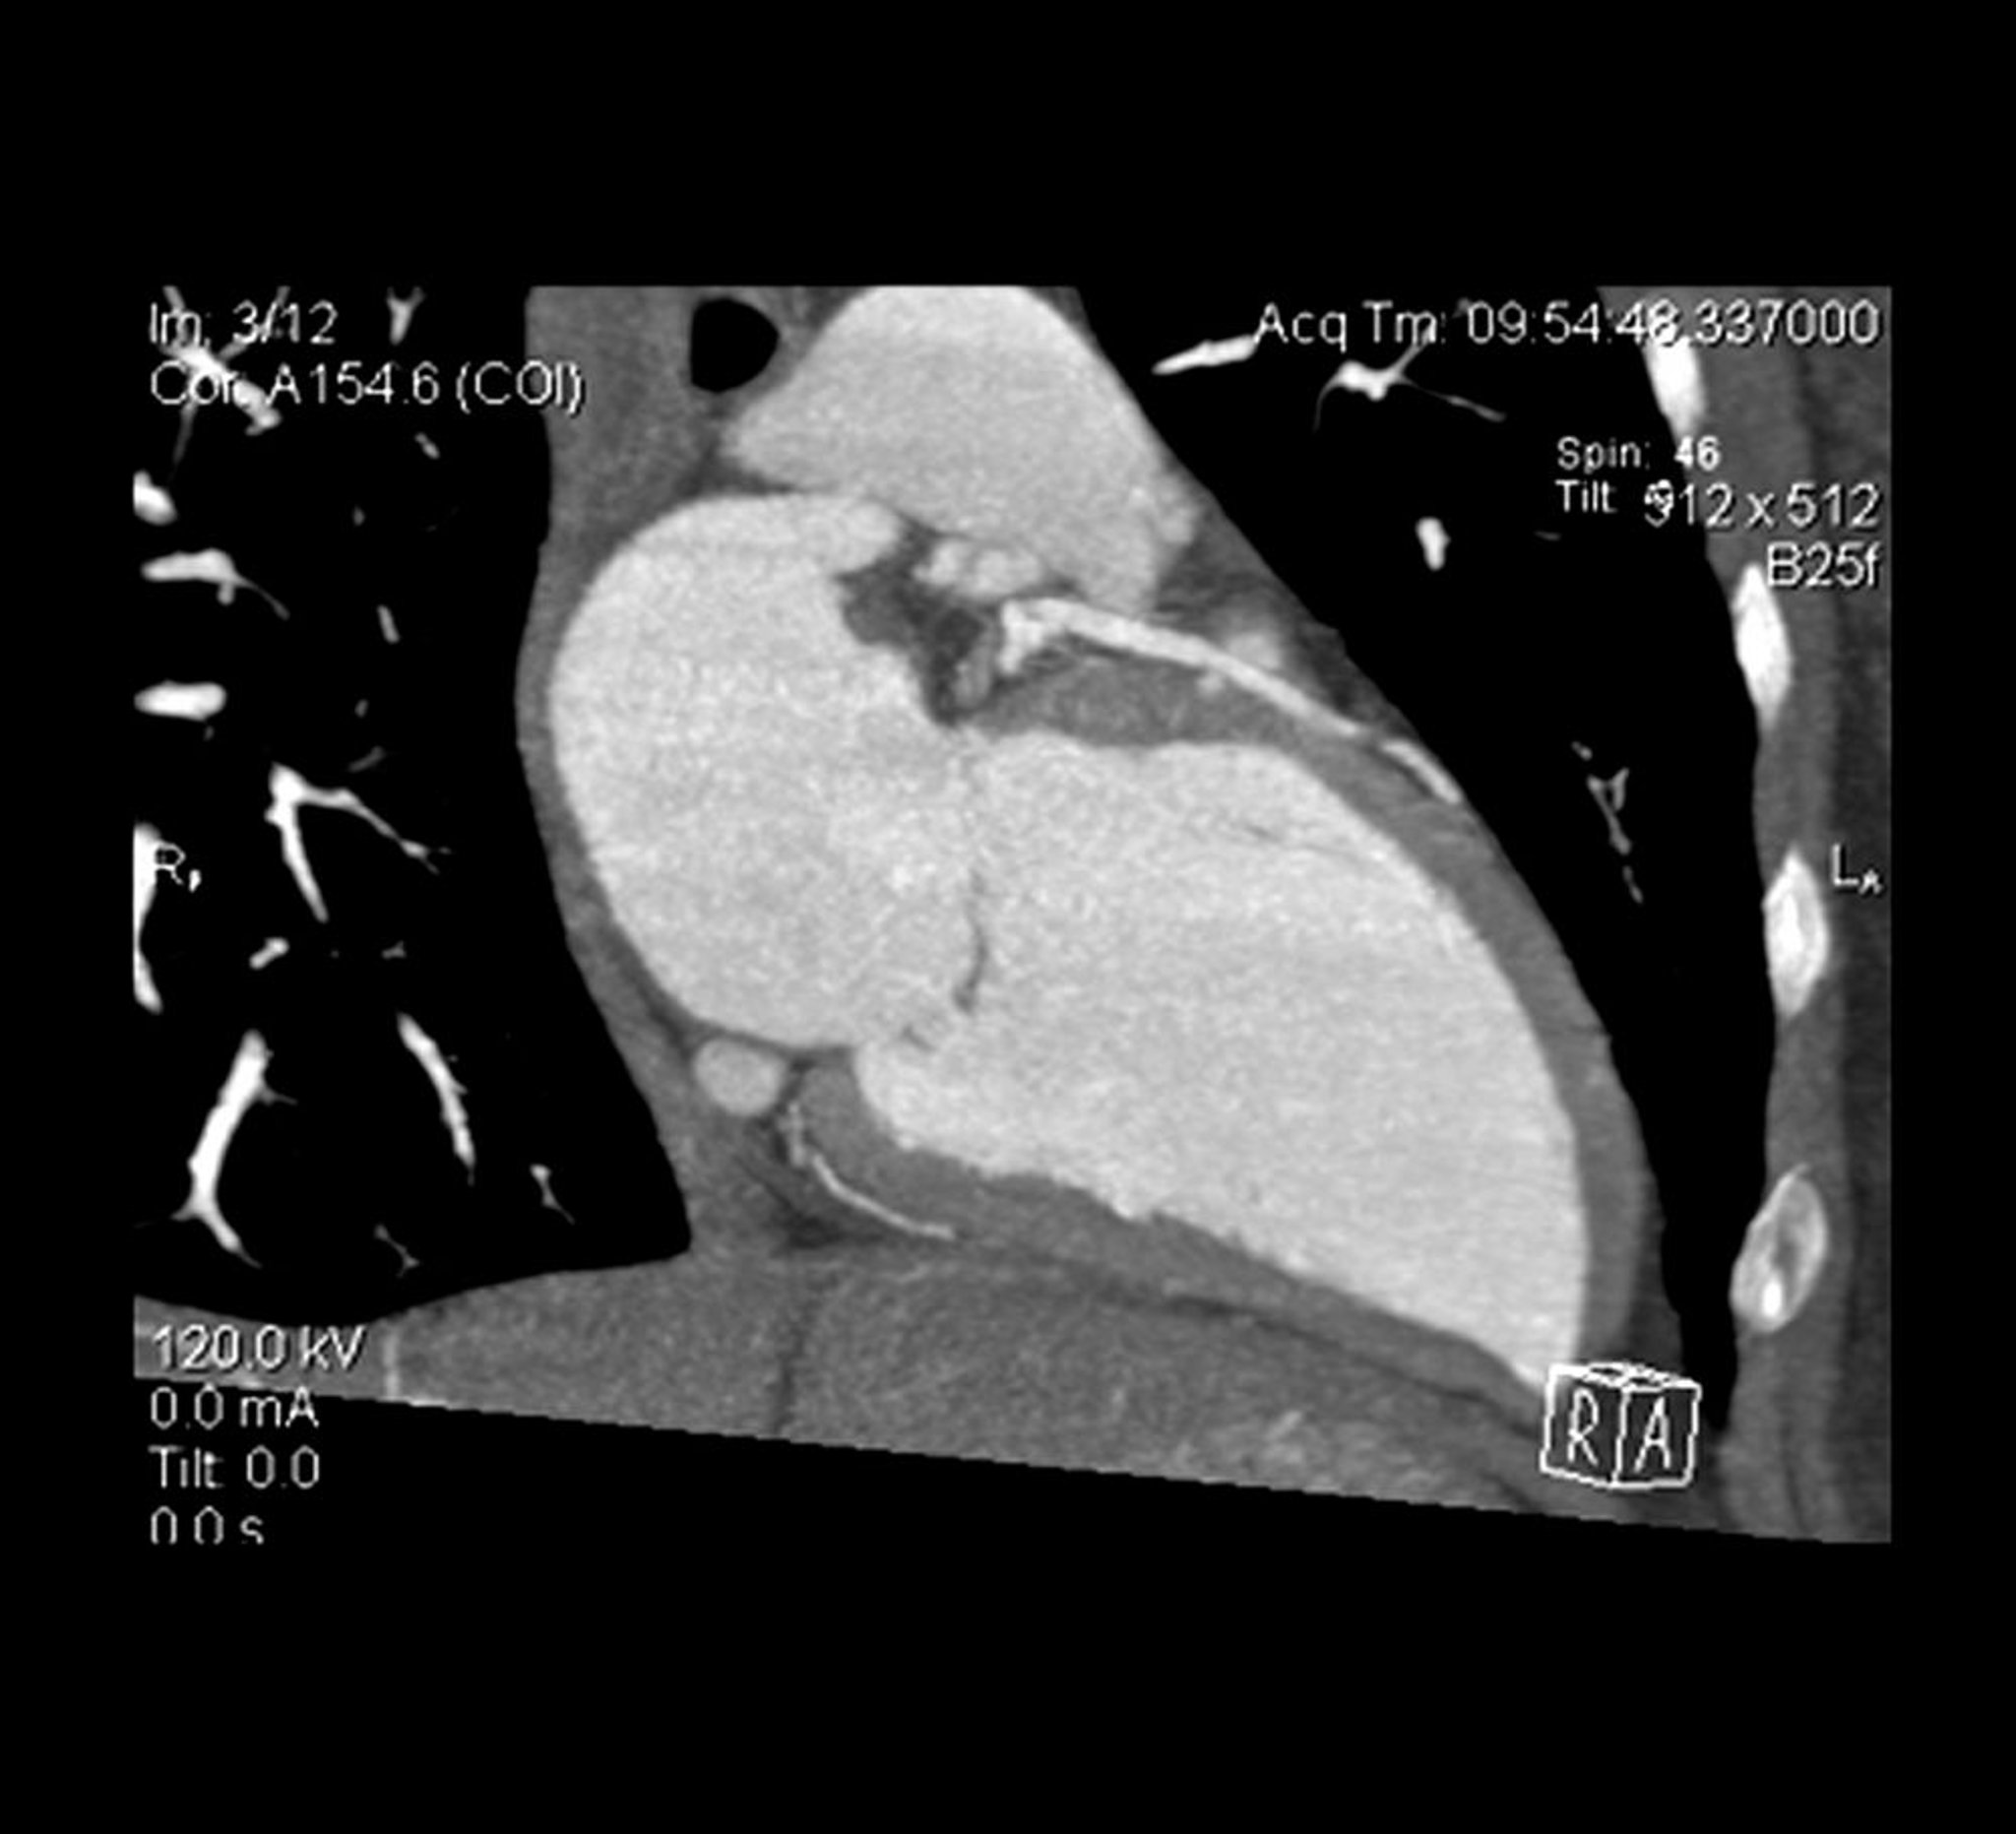

Die Querschnittsansicht eines Herz-CT-Angiogramms zeigt den linken Ventrikel und die linke absteigende Arterie.